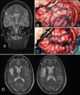

Familial diffuse cortical dysplasia

Pachygyria